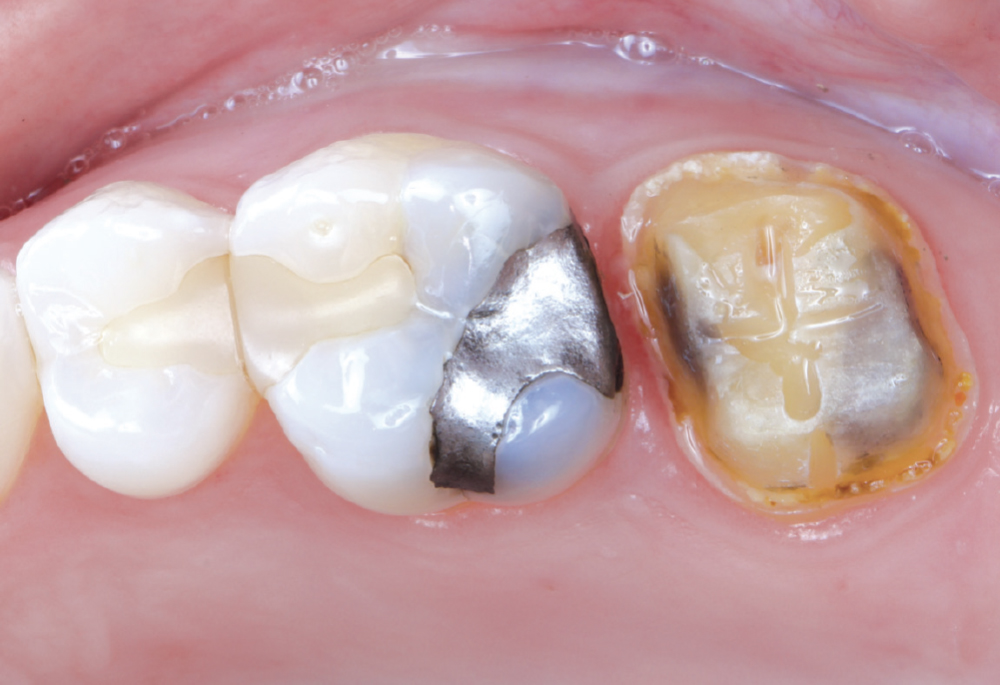

The patient’s chief concern was an open mesial margin of the crown on tooth #15

Figure 1: The patient’s chief concern was an open mesial margin of the crown on tooth #15, which was causing gingival inflammation and shredding her dental floss.

The crown was a 20-year-old Captek™ PFG high-noble bilayered restoration

Figure 2: The crown was a 20-year-old Captek PFG high-noble bilayered restoration.